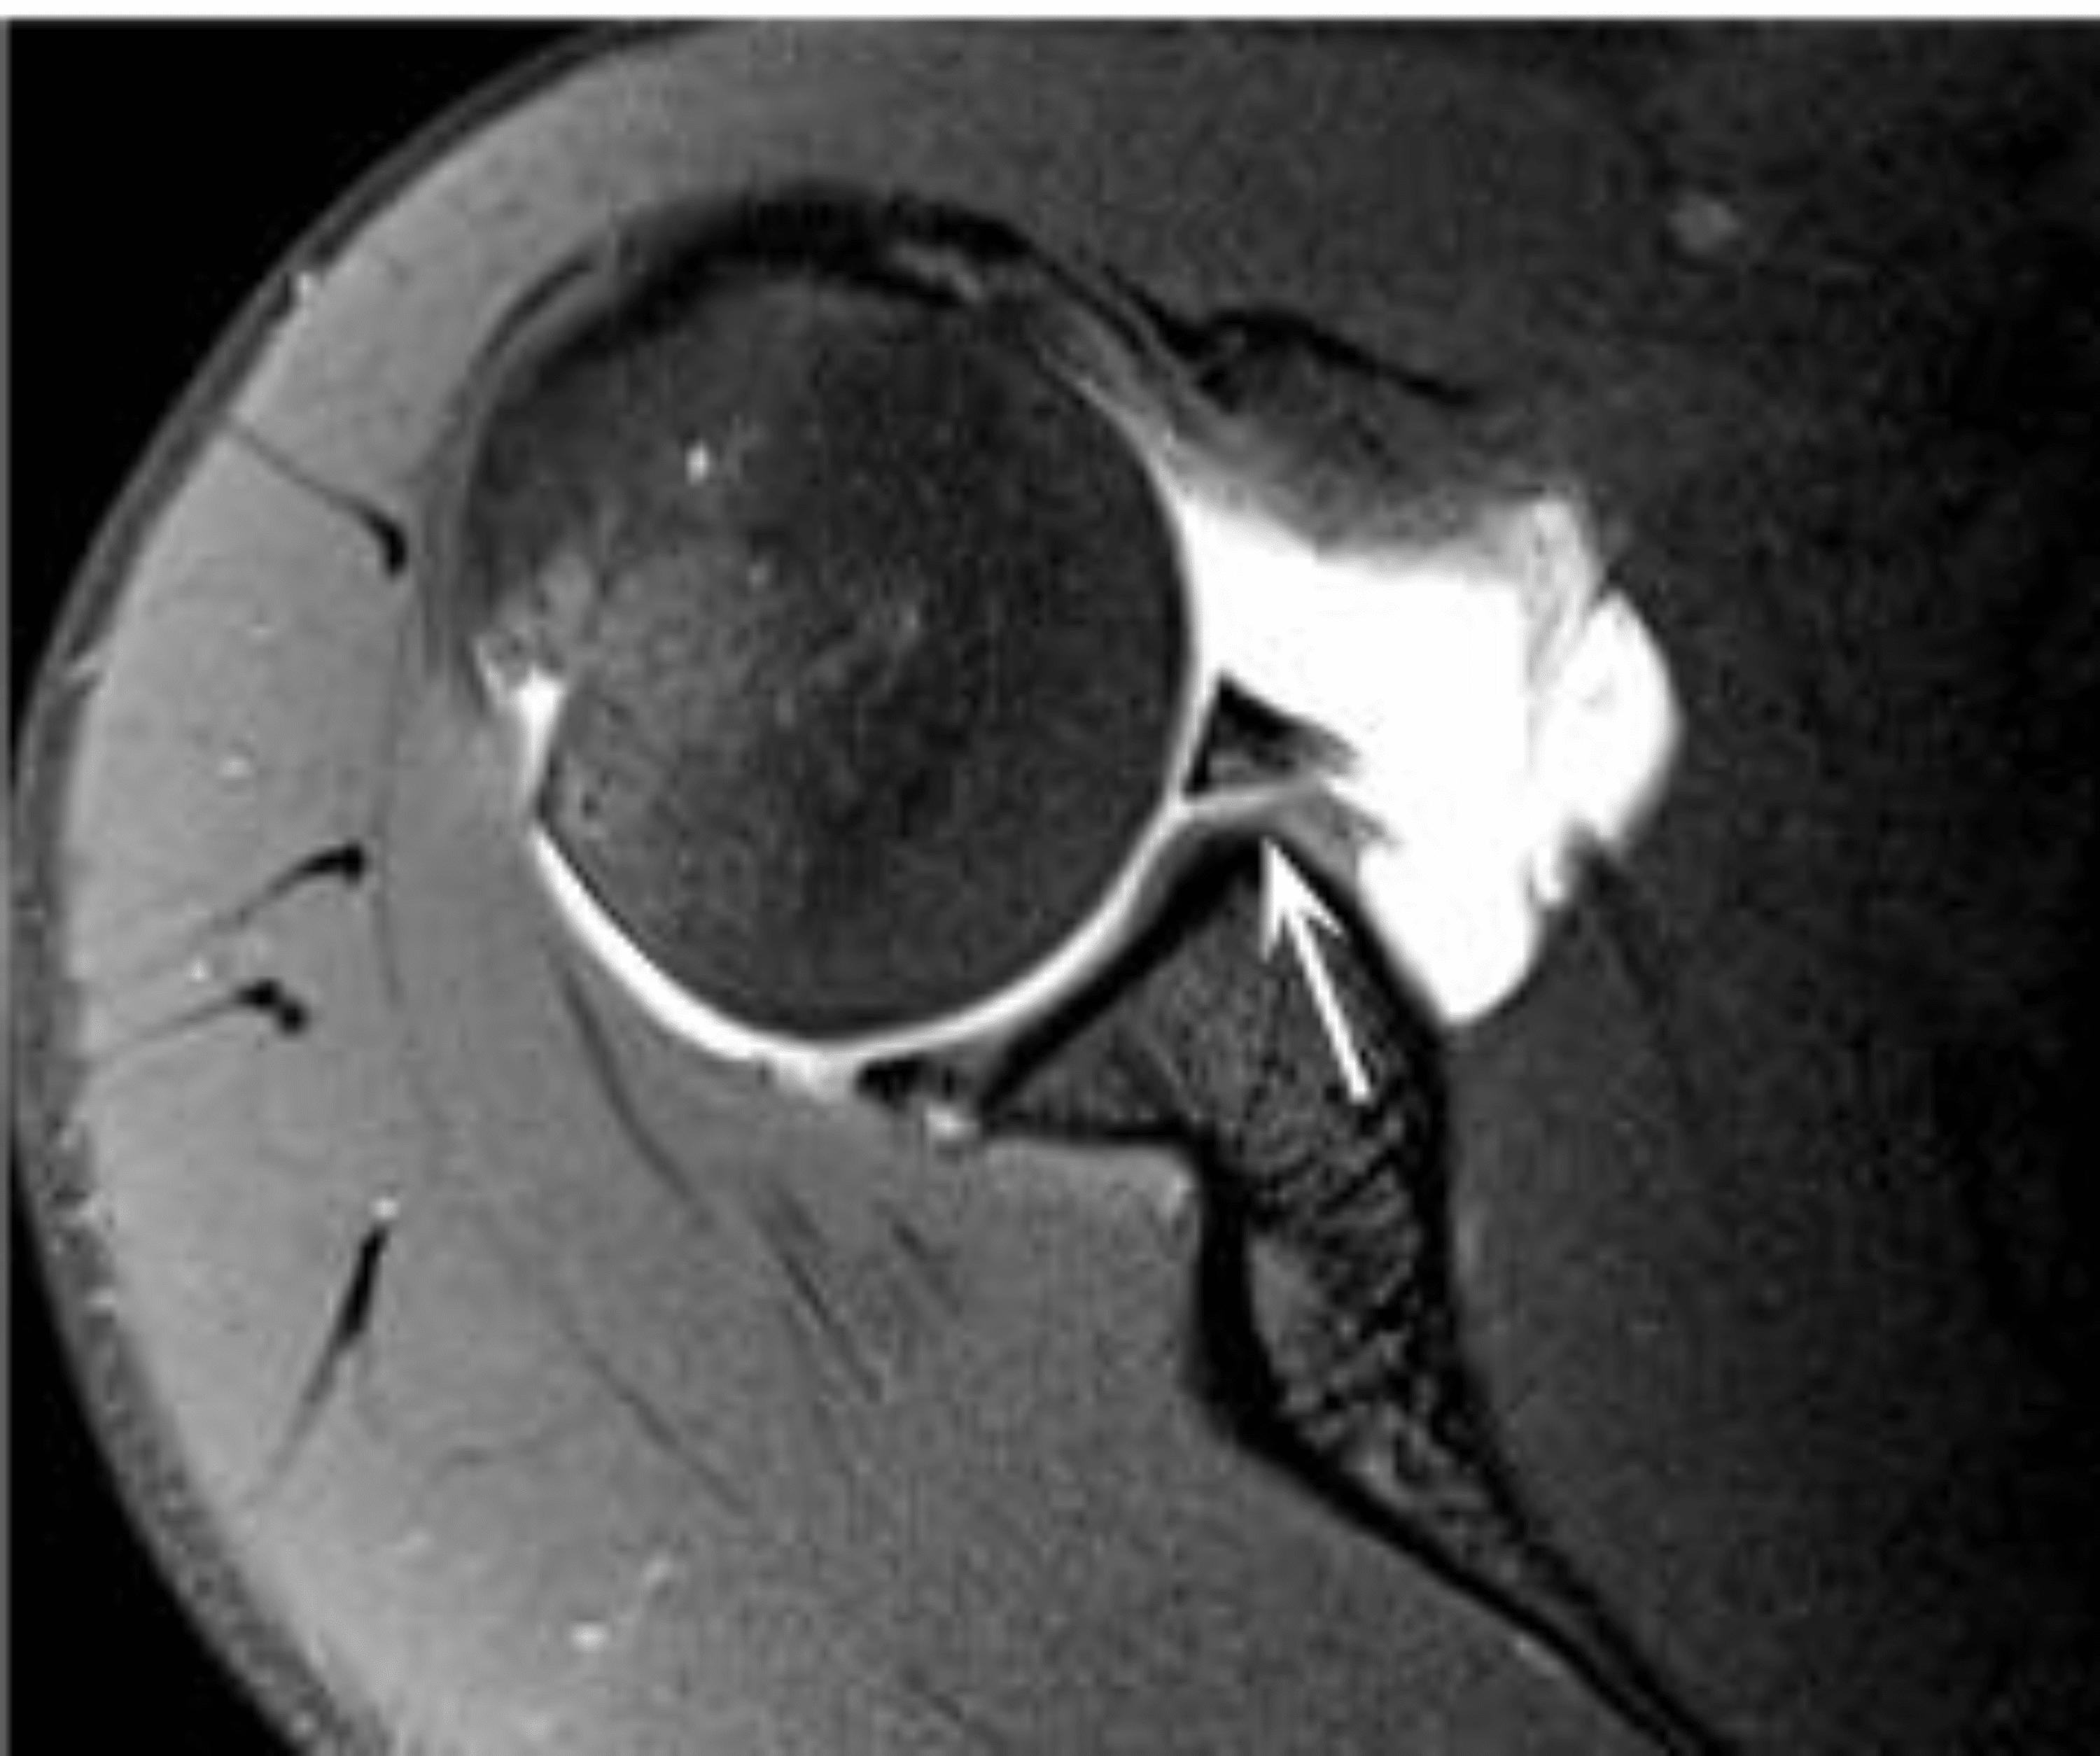

From www.researchgate.net

A 22yearold male collegiate football player with a right posterior Throwing A Football After Labrum Surgery Suffering a labral tear can be a setback for athletes and active individuals. In addition to eliminating pain and inflammation, the rehabilitation process for throwing athletes must include the restoration of motion, strength, and endurance, as well as restoration of proprioception, dynamic stability, and neuromuscular control. Slap repairs, once the standard surgical approach, involve reattaching the torn labrum to the. Throwing A Football After Labrum Surgery.